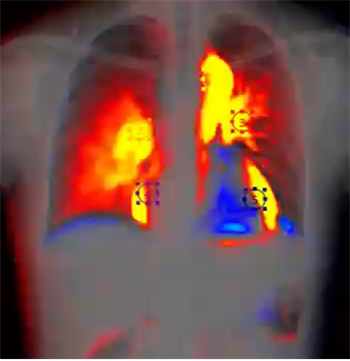

影像动态化可谓是近年来临床最火热的研究方向之一,与常规的静态平片不同的是,这项技术让临床平片“动”起来,但不仅仅只是“动”起来。在一个时间单位内低剂量高速获取多帧X线影像,得到连续动态摄影图像,看动态图像,不仅仅是看的更“准”一点,更多的是,影像诊断方式,向功能化上更进了一步。

能够最直观体会到动态DR直接的优势是,规避组织混叠的影响,相比于单张的图片,即使是一小段动态影像,也对确定诸如结节、细微骨折的病灶更有裨益的。更重要的层面是,这项技术让数字化X光摄影从二维解剖成像向运动成像、器官功能成像迈进。未来这项技术如果结合高级图像算法和人工智能/大数据,那将是是目前发展上限最高、潜力最大的技术路线,很有可能会成为革命性的下一代影像诊断主流方案。而搭载了动态影像功能的移动X线机毫无疑问将重新定义移动X线机。

又例如,老慢支、肺气肿、膈麻痹的患者往往呼吸功能不足,通过移动动态DR够对患者的呼吸运动功能做定量分析。给急诊、ICU中患者的呼吸运动功能的评估提供更加直接的影像证据。通过动态成像采集到的肺容积的信息,流速、流量等等信息,以及肺部的投影面积的信息,实时、准确、迅速、直观地监控肺通气状态,监控肺缺血缺情况,快速响应,在危急时刻及时发现并挽救急性肺栓塞患者。